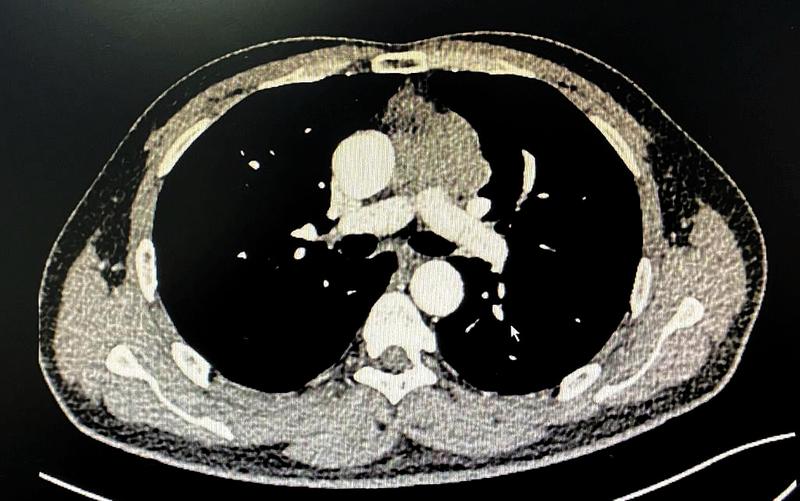

病例2:术后复查胸部X线

另一位女性患者发现左前胸壁肿物1周就诊,胸部CT示胸壁及前纵隔可见不规则软组织密度影,大小约48mmx40mm,长径约10cm,病灶与临近胸骨及左侧第2、3肋软骨分界不清。行超声引导下肿物穿刺活检,病理显示间叶来源肿瘤。肿瘤突破纵隔,侵犯了部分胸骨、左侧肋软骨以及胸部肌肉组织,此类型病例较少见,需切除部分受损胸骨及肋软骨,并对缺损的胸壁进行重建。由于缺损处较大,合适胸肋骨重建材料(如相应钢板和3D打印材料)价格昂贵,病人经济状况不能承担,李少民主任利用现有的胸骨钢板、肋骨环抱器以及经李少民主任改良的勾状的肋骨环抱器进行拼接,解决了长度的问题,稳定性上也表现出色,完美地重建了胸廓的完整性。手术入路也开创性的选择了胸腔镜和传统开胸手术结合的方式,从剑突下进行微创手术游离肿瘤的两侧及基底部,再从左侧胸壁开口,完整切除胸壁受侵组织,然后像打开“盖子”一样,移除肿瘤,避免了正中劈开胸骨的巨大创伤。手术过程顺利,术后恢复良好。